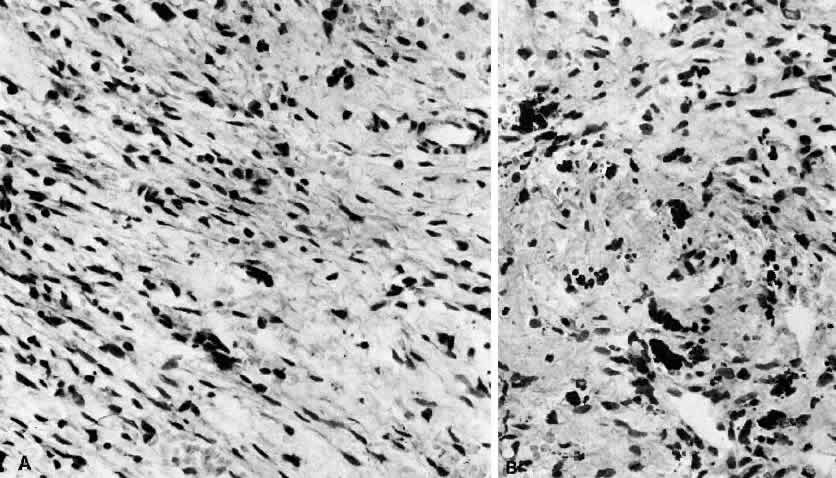

BENIGN LYMPHOEPITHELIAL LESION

Lacrimal gland enlargement in the absence of systemic disease without dry eye symptomatology has been termed benign lymphoepithelial lesion.3,107 Previously this entity was known as Mikulicz's syndrome or disease. However, due to confusion as to the exact definition of these terms, they have been abandoned. Histologically this condition is characterized by sheets of lymphocytes and plasma cells that replace the normal acinar and ductular structure of the gland (Fig. 8). Lymphoid follicles may be present. The remaining ductular elements may proliferate to form solid nests of cells outlined by excessive basement membrane production. Hyalinization may sometimes occur within these ductular remains. The cells within these nests are for the most part epithelial elements of the ducts. These structures are commonly called myoepithelial islands because of the incorrect belief that normal ducts have myoepithelial cells present in their wall. This has been disproved on electron microscopic evaluation.108 On superficial examination these formations may resemble lymphoid follicles. The presence of these ductular nests helps to differentiate this disorder from lymphomatous involvement of the gland, which is not associated with these structures. From one third to one half of patients with Sjögren's syndrome may have similar nests of ductular elements. The difference between benign lymphoepithelial lesion and idiopathic orbital inflammation (inflammatory “pseudotumor”) involving the lacrimal gland is based on the more monomorphic infiltrate seen in benign lymphoepithelial lesion in contrast to the relatively more polymorphic infiltrate seen in “pseudotumor.” In addition, “pseudotumor” contains more plasma cells and fibrotic tissue and is associated with lymphoid follicles with active germinal centers. Finally, the lacrimal gland capsule is usually preserved in benign lymphoepithelial lesion in contrast to inflammatory “pseudotumor,” which is a more destructive process.

Fig. 8. Epimyoepithelial island is composed of cytologically benign cells that have retracted from surrounding inflammatory infiltrate. Island is indicative of an inflammatory disorder and weighs heavily against interpreting lymphocytic infiltrate as lymphoma (H&E, 76% of ×320).